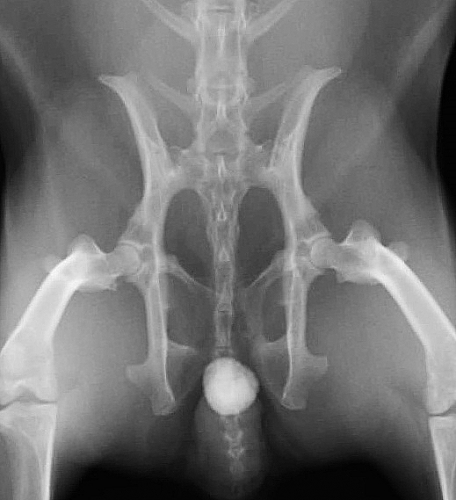

下の写真は膀胱結石が尿道結石となり尿路閉塞を生じた一連の変化をレントゲンで撮影したものです。数週間にわたる血尿と「排尿時のしぶり」と頻回尿を症状とする排尿障害を起こしていたウサギのものです。レントゲン検査では1cm程の膀胱結石が確認されました。

膀胱炎にやそれに伴う頻尿などの諸症状に対する対症療法を行ってもあまり症状の改善がみられないため、手術を計画しましたが、その前に排尿困難に陥って緊急で来院した際のレントゲン写真が下の二枚です。膀胱内にあった結石が尿道結石となり急性の尿路閉塞を生じています。

このように上流でつくられた結石が下流へ流れ、そこで急性の尿路閉塞を生じるということが、尿路結石症の最も激しい症状を引き起こします。尿路閉塞に対しては結石の閉塞状態をはじめ、腎機能の評価をはじめとする全身の評価と緊急手術を含めた閉塞解除に関わる治療を並行して迅速に行わなければなりません。

上写真のウサギは緊急の尿道切開術によって尿道結石の摘出を実施いたしました。